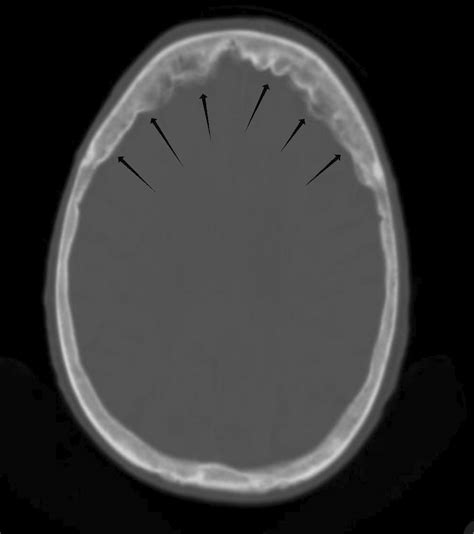

Hyperostosis frontalis interna (HFI) is a condition characterized by a benign, symmetrical thickening of the inner table of the frontal bone of the skull. While the term might sound intimidating, it is a relatively common radiological finding, often discovered incidentally during imaging scans performed for other reasons, such as headaches or minor head trauma. Understanding this condition is important for clinicians and patients alike, particularly because it can sometimes be associated with hormonal or metabolic factors, although its exact clinical significance remains a subject of ongoing research.

At its core, Hyperostosis frontalis interna manifests as bony growths—known as osteomas or nodular projections—on the inner surface of the frontal bone. Unlike malignant skull conditions, these deposits are benign and generally do not extend into the brain tissue itself. They are most frequently identified through computed tomography (CT) scans or magnetic resonance imaging (MRI) of the head.

- Symmetry: The bony overgrowths are typically present on both sides of the inner frontal bone.

- Imaging: A CT scan is the gold standard for visualizing bone density and structure, making it the most effective tool for confirming HFI.